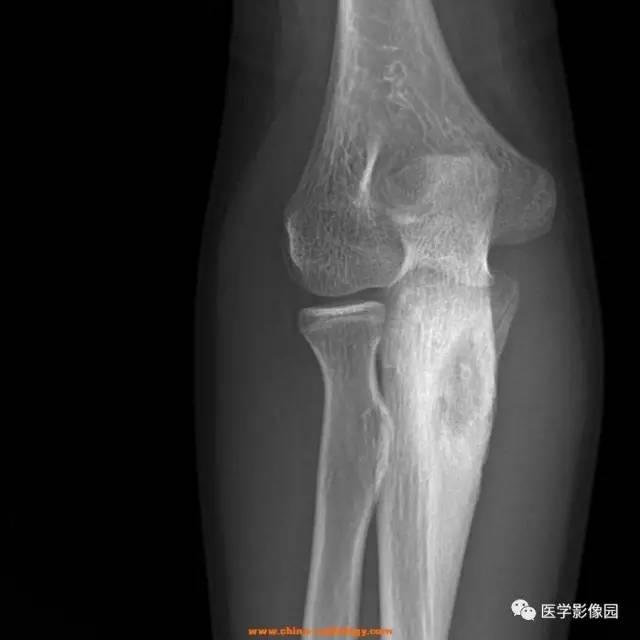

骨样骨瘤的影像诊断

544x650 - 39KB - JPEG